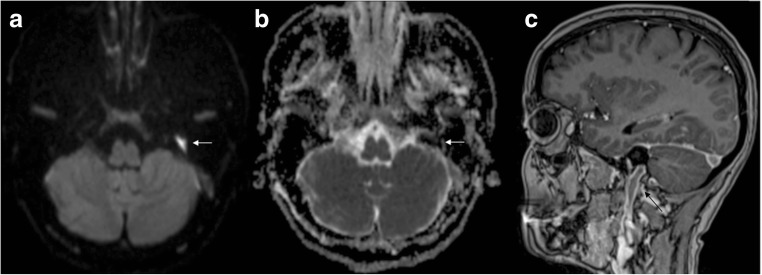

Fig. 2.

Spinal cord ischaemia. High T2 signal abnormality in the conus medullaris with diffusion restriction on DWI (arrows) compatible with an ischaemic lesion